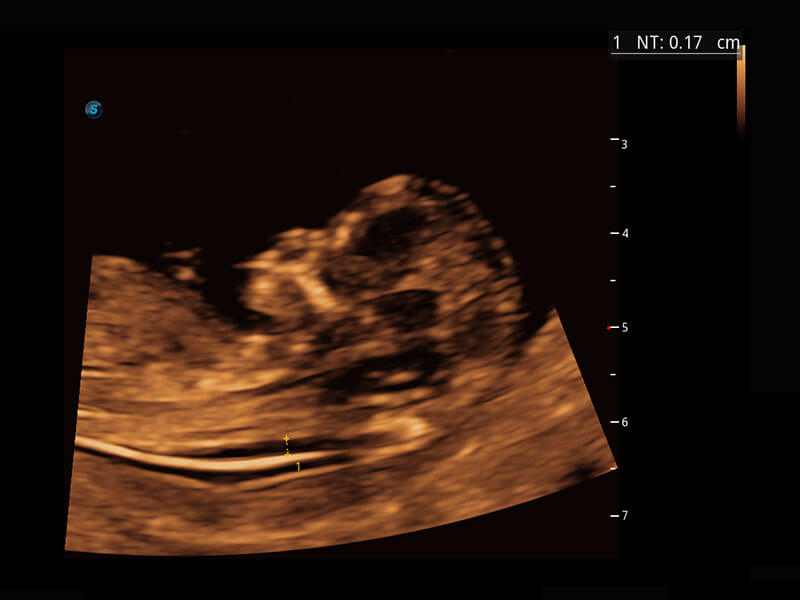

P60在胎儿早孕期超声筛查中为您带来优异的图像质量。

高分辨率容积成像-早孕胎儿

光影成像-孕囊